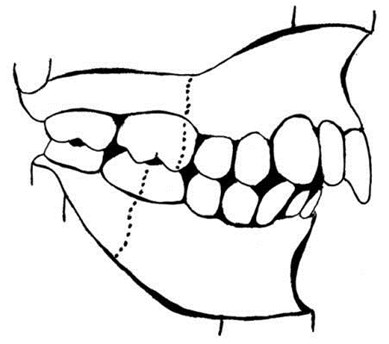

Illustration #2 of 3: End-to-End Class II Molar Relationship

This example demonstrates an end-to-end molar relationship which satisfies ABO criteria for Initial Certification only. It is to be distinguished from the full-step Class II of the preceding illustration.

Illustration #3 of 3: Molar Relationships